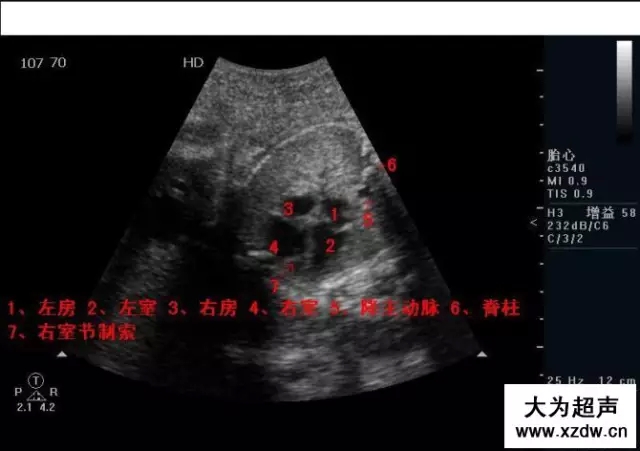

產(chǎn)科超聲正常圖片